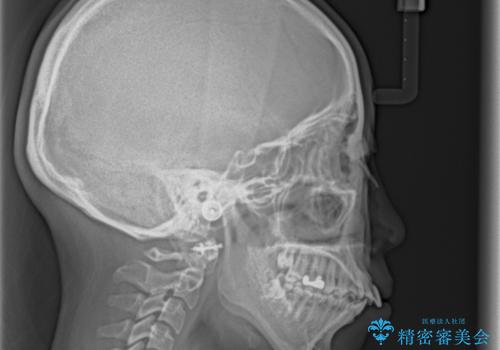

突出した口元が気になる ハーフリンガル装置による抜歯矯正

- 口元の突出感を気にして来院された患者様です。

通常では上下左右の第一小臼歯4本を抜歯しますが、下顎が左側にシフトしていたため、下顎左側のみ第二小臼歯を抜歯し、正中を合わせながら口元を下げる治療計画としました。

ハーフリンガルは、通常では表側のワイヤー矯正よりも治療期間がかかります。特に今回のように下顎左側をイレギュラーの第二小臼歯抜歯としたため、さらに時間がかかることが予想されました。

実際に治療をおこなってみると、2年を切る短期間で治療を終えることができました。